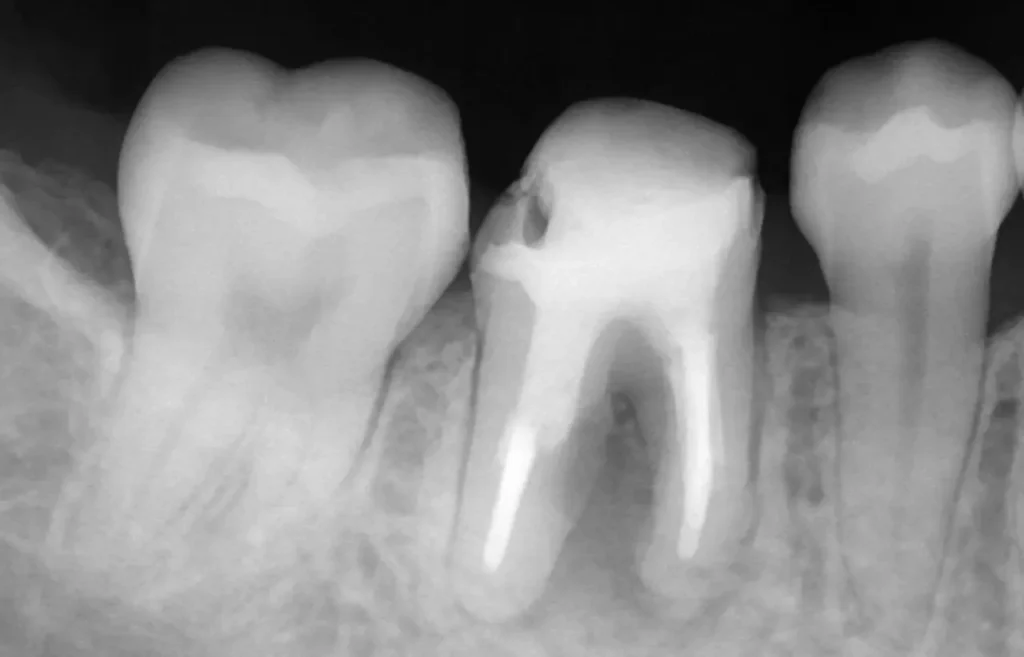

自費根管治療症例2 治療前

左下の奥歯が根の治療を受けているが治らない。

初診時

管の分かれている部分に根の治療による穿孔がありました

術中

穿孔部分の封鎖と通常の根管治療を行いました

術後

症状は、完全に消えて、穿孔部分の封鎖と確実な清掃、充填が確認できます